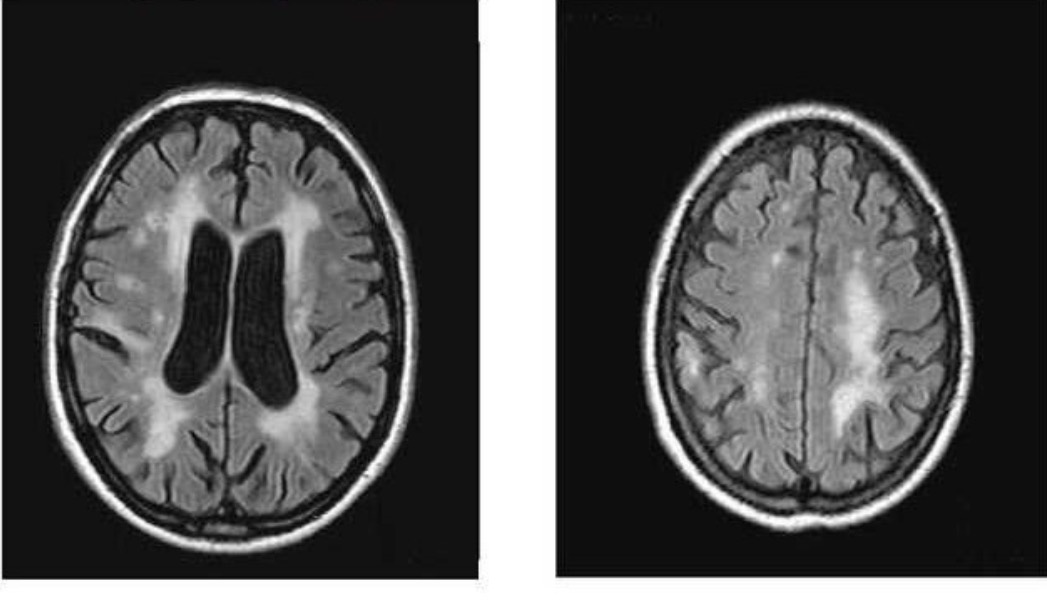

Лейкоариоз на МРТ: Что делать? Пошаговая инструкция

Если в заключении МРТ головного мозга вы увидели слово «лейкоариоз» (или «перивентрикулярный лейкоариоз»), не паникуйте. Это не приговор, а важный сигнал, который говорит об изменении белого вещества мозга. Чаще всего это признак нарушения кровоснабжения мелких сосудов.

1.  О локализации и степени: «Насколько выражен лейкоариоз по шкале Fazekas (1, 2 или 3 степень)? Он вокруг желудочков или более диффузный?» Это говорит о серьезности изменений.